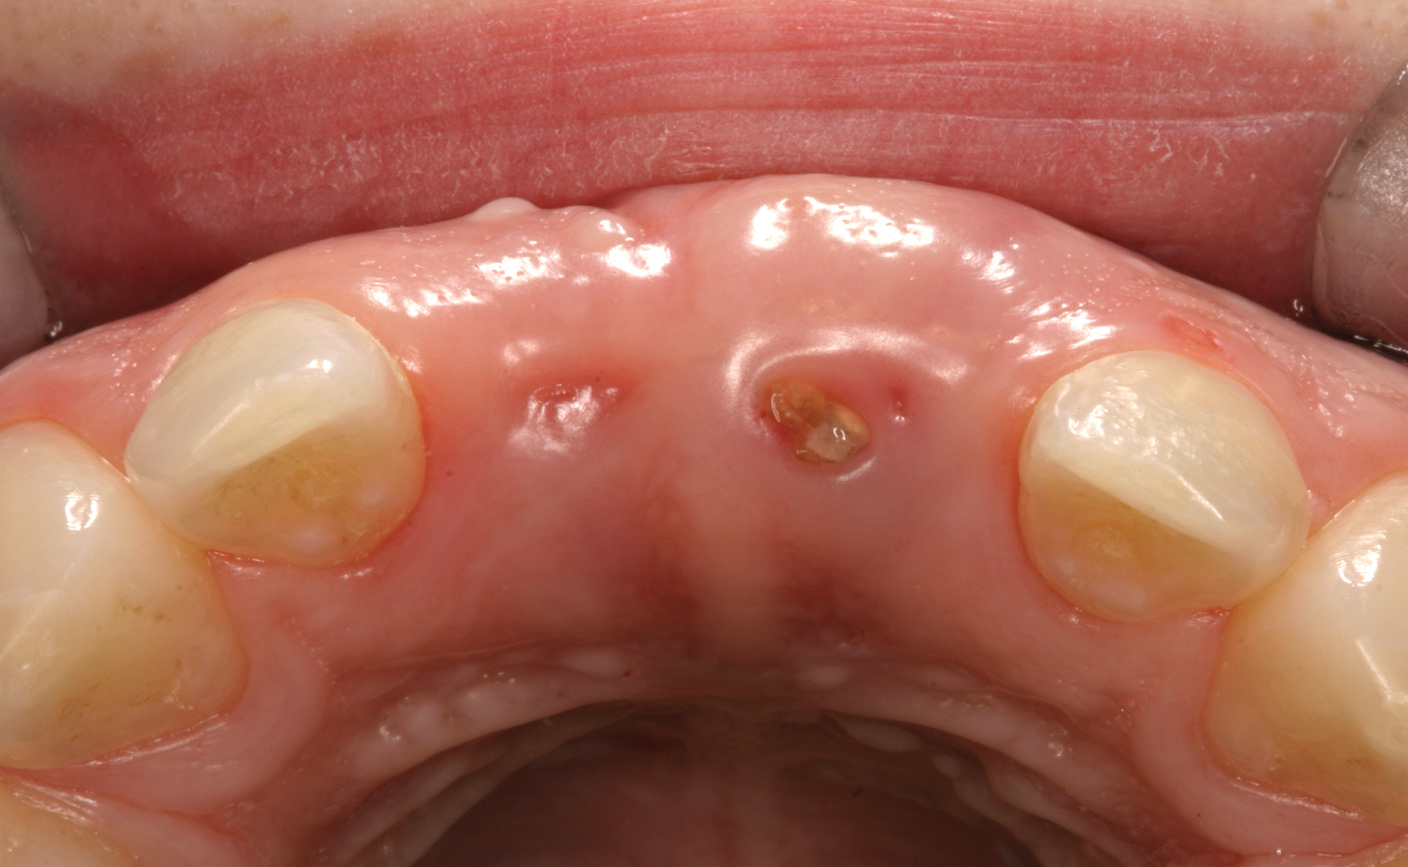

Fig 11. Age 20. Extraction sites with intact labial plates. Their vertical height was near the level of the proximal bone of the adjacent teeth.

Figure 11

After that the patient was seen in the endodontic office periodically to monitor the retained roots and associated alveolar ridge. The root of No. 8 was retained for 8 years after fracturing, and the root of No. 9 was retained for 9 years. During that time there were no clinical signs or symptoms, nor were there radiographic signs of periradicular breakdown. A final endodontic check at age 19 found the coronal surface of the root of No. 9 had been exposed. The vertical level and horizontal width of the alveolar ridge appeared very similar relative to the adjacent teeth as it had been at ages 10 and 15 (Figure 8 and Figure 9). No evidence of periradicular breakdown appeared radiographically (Figure 10). The patient's growth was deemed nearly completed and he was referred to an oral surgeon for evaluation and placement of implants.

At age 20, an oral surgeon placed implants in the Nos. 8 and 9 sites. A full-thickness flap was reflected and the roots were extracted.  Both sockets were intact with thin-medium width labial plates (Figure 11). Implants were placed into the sockets, healing abutments were secured, and the flaps were sutured. Four months later the implants were uncovered and restorations were completed. (Author's note: A radiograph of the implants with healing abutments at placement was unavailable for this article.)